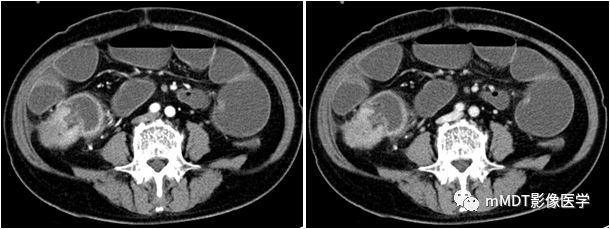

病例6:男,78岁,腹痛2周,发现腹腔占12天,弥漫性大B细胞淋巴瘤

qw10.jpg

CT表现:回肠末端见肿块影,密度均匀,增强后轻度均匀强化。

病理:(小肠)弥漫性大B细胞淋巴瘤。

CK-广(-);CD20(++);CD79α(++);CD3(部分+);CD45RO(+);

CD10(+);BCL-6(+);Mum-1(+);CD5(+);EBV(-);

Ki-67(>90%阳性);BCL-2(+);CD34(-);CD117(±)。